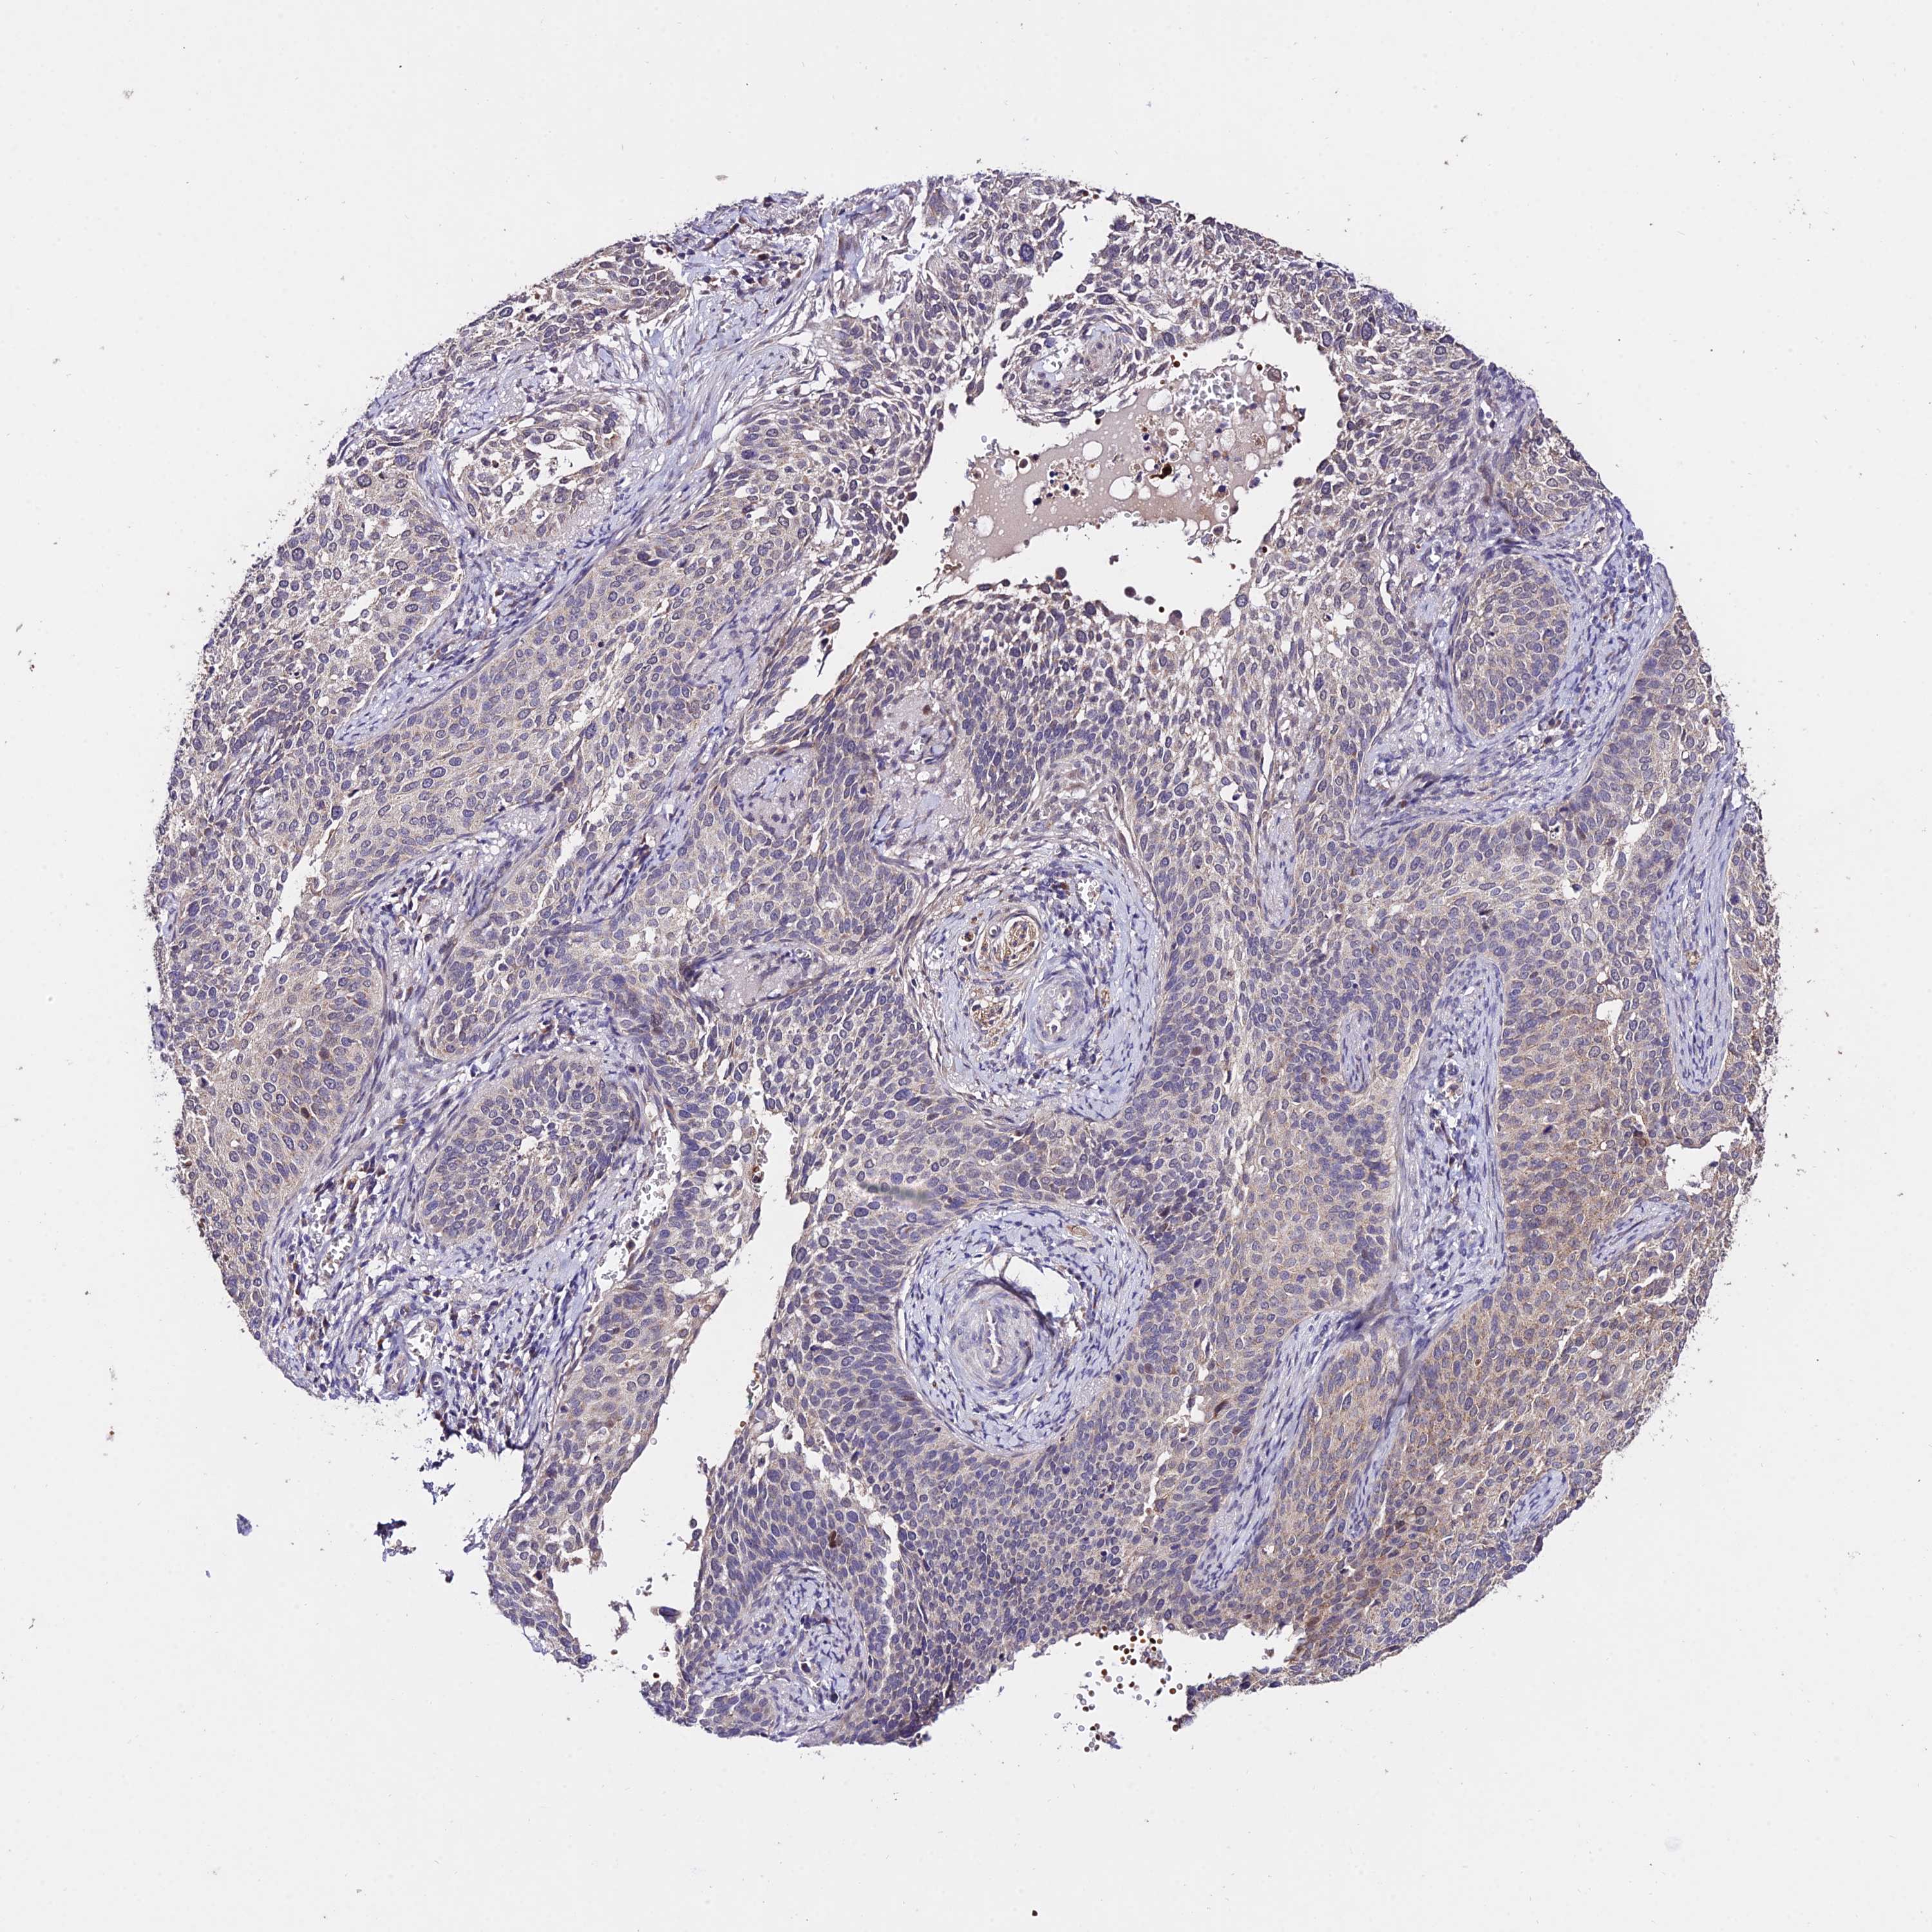

CERVICAL CANCER - Protein expressioni

A mouse-over function shows sample information and annotation data. Click on an image to view it in a full screen mode. Samples can be filtered based on level of antibody staining by selecting one or several of the following categories: high, medium, low and not detected. The assay and annotation is described here.

Note that samples used for immunohistochemistry by the Human Protein Atlas do not correspond to samples in the TCGA dataset.

Antibody stainingi

Antibody staining in the annotated cell types in the current human tissue is reported as not detected, low, medium, or high, based on conventional immunohistochemistry profiling in selected tissues. This score is based on the combination of the staining intensity and fraction of stained cells.

Each image is clickable and will lead to virtual microscopy that enables deeper exploration of all samples and also displays staining intensity scores, fraction scores and subcellular localization as well as patient and tissue information for each sample.

Antibody HPA042994

Staining

High

Medium

Low

Not detected

Intensity

Strong

Moderate

Weak

Negative

Quantity

>75%

75%-25%

<25%

None

Location

Nuclear

Cytoplasmic/membranous

Cytoplasmic/membranous,nuclear

Squamous cell carcinoma, NOS

Adenocarcinoma, NOS